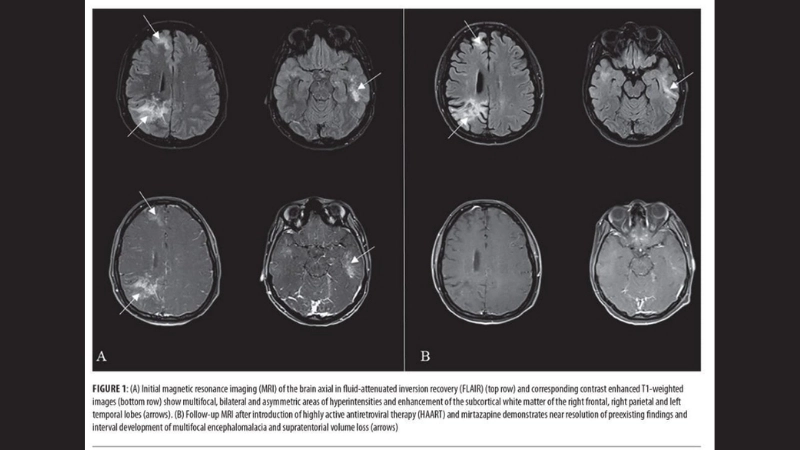

PML diagnosis relies on MRI and JC virus detection